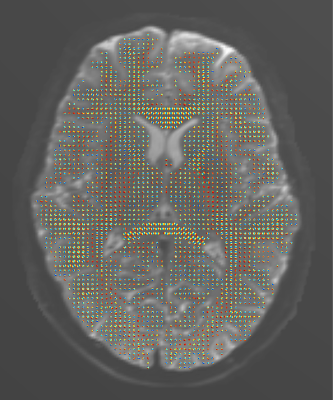

Figure 4. Diffusion tensor ODFs of the ex vivo human brain hemisphere. We scanned the sample on a 3T scanner (MAGNETOM Skyra, Siemens Healthcare, Erlangen, Germany) using the STE sequence with the long diffusion time of 1 second (TE/TR=33/26200 ms), the b-value of 1000 s/mm², and isotropic voxel size of 2 mm. To increase the signal-to-noise ratio (SNR), we acquired and averaged 8 repetitions of each of the 256 diffusion directions, as well as 320 repetitions of the b=0 image (shown in the background).